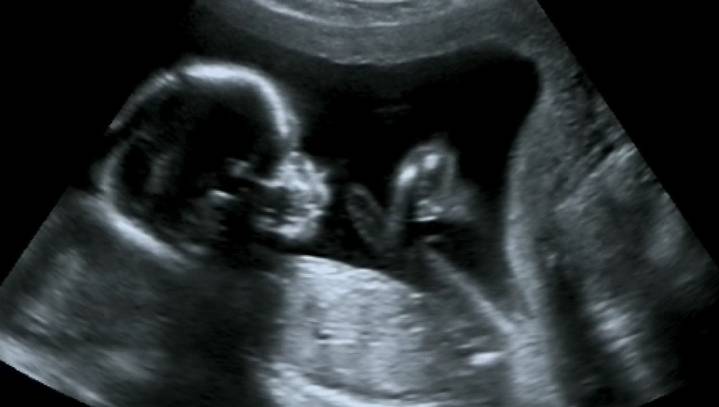

Update: 3,000 New Deaths Today But Enough About Abortion The Babylon Bee2 hrs agoFollow Share to:Update: 3,000 New Deaths Today But Enough About Abortion .See Full Page97